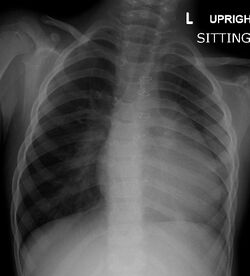

A chest X-ray of a child with tetralogy of Fallot

There are three different useful diagnostic tests used for the diagnosis of tetralogy of Fallot.[48] These include a chest radiograph, electrocardiogram, and echocardiogram.[48] The echocardiography determines the final diagnosis and typically offers enough information for surgical treatment planning.[48] About half of all patients are now diagnosed before they are born.[48] Differential diagnosis is when physicians diagnose between two or more conditions for a person's symptoms and this can include primary pulmonary causes of cyanosis, cyanotic heart lesions, pulmonary stenosis and transposed arterial trunks.[48]

Chest radiograph

Before more sophisticated techniques became available, chest X-ray was the definitive method of diagnosis. The abnormal "coeur-en-sabot" (boot-like) appearance of a heart with tetralogy of Fallot is classically visible via chest X-ray, although most infants with tetralogy may not show this finding.[49] The boot like shape is due to the right ventricular hypertrophy present in TOF. Lung fields are often dark (absence of interstitial lung markings) due to decreased pulmonary blood flow.[50]:171–72